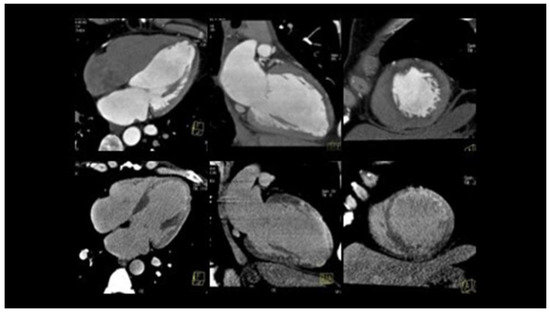

Chronic or Changeable Infarct Size after Spontaneous Coronary Artery Dissection

by Gordana Krljanac, Svetlana Apostolovic, Zlatko Mehmedbegovic, Olga Nedeljkovic-Arsenovic, Ruzica Maksimovic, Ivan Ilic, Aleksandra Djokovic, Lidija Savic, Ratko Lasica and Milika Asanin

Diagnostics 2023, 13(9), 1518; https://doi.org/10.3390/diagnostics13091518 - 23 Apr 2023

Spontaneous coronary artery dissection (SCAD) could be the cause of acute myocardial infarction (AMI) and sudden cardiac death. Clinical presentations can vary considerably, but the most common is the elevation of cardiac biomarkers associated with chest discomfort. Different pathological etiology in comparison with [...] Read more.

Spontaneous coronary artery dissection (SCAD) could be the cause of acute myocardial infarction (AMI) and sudden cardiac death. Clinical presentations can vary considerably, but the most common is the elevation of cardiac biomarkers associated with chest discomfort. Different pathological etiology in comparison with Type 1 AMI is the underlying infarct size in this population. A 42-year-old previously healthy woman presented with SCAD. Detailed diagnostical processing and treatment which were performed could not prevent myocardial injury. The catheterization laboratory was the initial place for the establishment of a diagnosis and proper management. The management process can be very fast and sometimes additional imaging methods are necessary. Finding predictors of SCAD recurrence is challenging, as well as predictors of the resulting infarct scar size. Patients with recurrent clinical symptoms of chest pain, ST elevation, and complication represent a special group of interest. Therapeutic approaches for SCAD range from the ”watch and wait” method to complete revascularization with the implantation of one or more stents or aortocoronary bypass grafting. The infarct size could be balanced through the correct therapeutical approach, and, proper multimodality imaging would be helpful in the assessment of infarct size. Full article